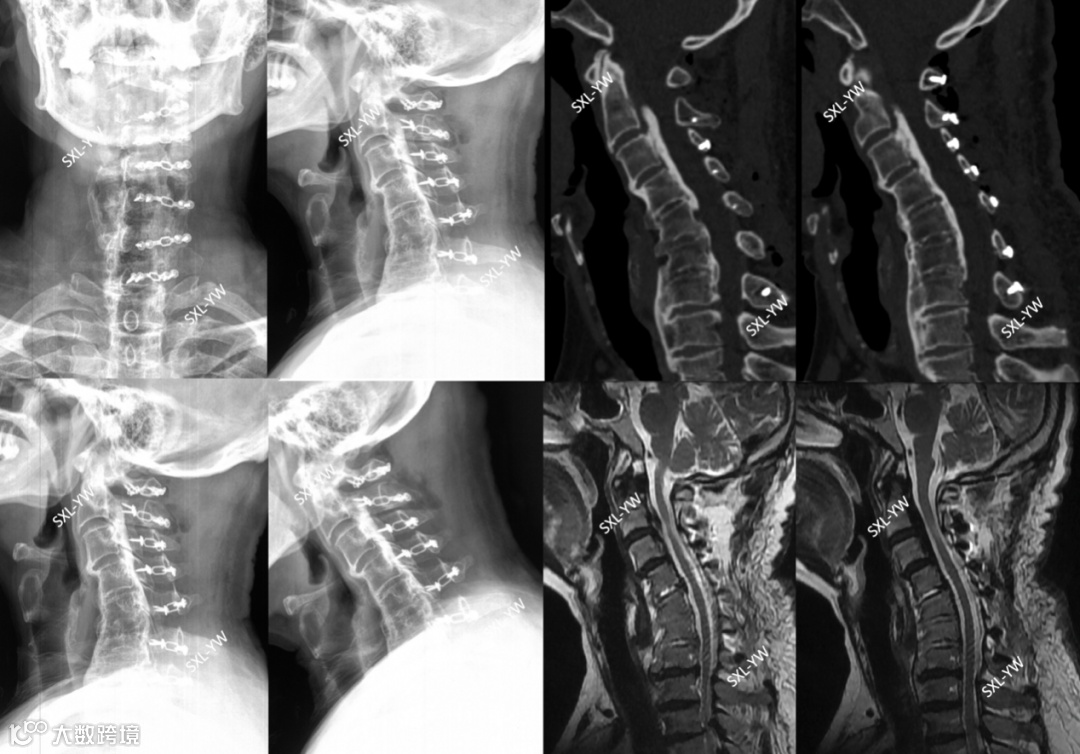

图14 K线与PCS评分的正面碰撞之二,术前影像。后凸25°、K线阴性,如果参考K线理论,这些都是单开门手术的禁忌、单开门术后脊髓漂移将不充分,事实会真的如此吗?该患者PCS评分为8分,单开门术后神经功能恢复的可能性大,建议行单开门手术。2个截然不同的指导意见,哪个才是正确的?

图15 K线与PCS评分的正面碰撞之二,术后影像。C1-7单开门术后脊髓获得充分漂移,后凸不影响脊髓漂移程度

上述病例证实:K线不能预测单开门术后脊髓漂移情况及神经功能的恢复情况;脊髓漂移程度与K线没有相关性;PCS评分具有预测神经功能恢复情况、指导手术方式选择、明确手术范围的作用。